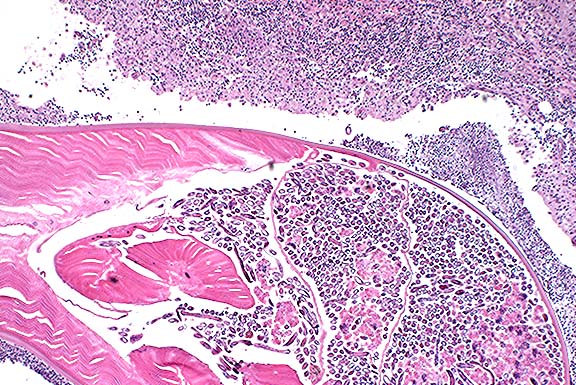

Case II - No label (AFIP 2549264)

Signalment: 11-year-old, spayed female, Cocker Spaniel, canine.

History: This 13-kg Cocker Spaniel presented to the referring veterinarian for nodules on the ventrum and rear limbs. The owner first noticed the nodules 1 week prior to presentation and became concerned since they were increasing in number and size. One nodule had an opening to the surface of the skin that drained a purulent exudate; a large parasite was expressed from the nodule. The dog was otherwise alert, active, and afebrile. Hematology and biochemical profiles were within normal limits and fecal flotation was negative. The dog was routinely treated monthly with oral ivermectin heartworm preventative. The dog lived in southwestern Wisconsin, but vacationed regularly in central Wisconsin near a spring-fed lake. The dog swam in that lake and periodically ate snails.

Gross Pathology: Subcutaneous nodules measuring 2-3 cm in diameter were palpable in the skin. The surrounding skin was erythematous. Nodules developed an opening that drained a purulent exudate. The largest nodules were surgically removed. The dog continued to develop additional nodules and, to date, 75 adult parasites identified as Dracunculus insignis have been removed.

Histopathology: A histologic section of a representative nodule reveals pyogranulomatous nodules localized in the deep dermis containing multiple cross sections of parasitic nematodes and numerous embryos, both in a large uterus and free in the exudate. The adults have a thick cuticle and a prominent coelomyarian musculature. In some sections, there is a small focus of epidermal ulceration with pyogranulomatous inflammation intermingled with embryos at the skin surface.

Contributor's Diagnosis: Dermatitis, pyogranulomatous, with adult nematodes and embryos, multifocal, severe, Dracunculus insignis.

Case 5-2. Dermis. Pyogranulomatous inflammation surrounding an adult Dracunculus insignis with larvae. 4X

AFIP Diagnosis: Haired skin, subcutis: Pyogranuloma, with intralesional adult female nematode and larvae, Cocker Spaniel, canine, etiology consistent with Dracunculus insignis.

Conference Note: This case was reviewed by C.H. Gardiner, PhD, veterinary parasitology consultant to the AFIP. He pointed out additional characteristics of the parasite which are evident in histologic section, including:

a. Prominent coelomyarian muscles found in two "bands" that are separated by large, low lateral chords.

b. Small intestine, identifiable by the presence of iron pigment in the epithelial cells.

c. Distinctive larvae that are prominently cross-striated and have very long tails containing phasmids (identified as "reddish circles" at the base of the tail).